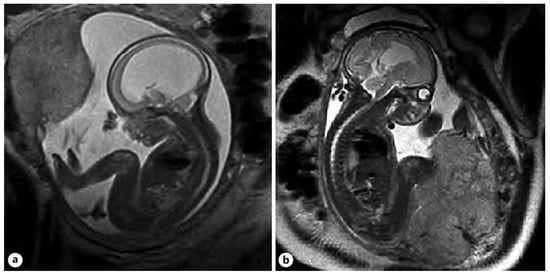

Figure 1. Imaging in the transventricular plane of ISVM at 22.3 weeks of pregnancy: (A) transabdominal ultrasound: the atrial width of the distal ventricle is increased at AD = 19.1 mm, and (B) MRI of T2-dependent sequence SSFSE.

Figure 2. ISVM fetal ultrasound before (A,B) after VAS implantation, arrow indicates VAS.

Sonographic evaluation remains the imaging test of choice due to its ease of application, test repeatability, low cost, and availability of the equipment at fetal medicine centers []. The standardized AD should be measured in the transventricular plane (axial) at the level that demonstrates the frontal horns and cavum septi pellucidi, in which the appearance of the hemispheres is symmetrical []. The caliper should be placed on the interior margin of the medial and lateral wall of the atria, at the level of parietal-occipital groove and glomus of the choroid plexus, on the axis that is perpendicular to the long axis of the left ventricle (Figure 1 and Figure 2). The measurements are perpendicular to the long axis of the left ventricle. In the case of fetal VM, the choroid plexus appears to be ‘dangling’ or falling towards the dependent ventricular wall and occupies less space in the ventricle than in cases without VM []. In cases without VM, the choroid plexus typically takes up at least half or more of the lateral ventricle []. Asymmetric VM is defined in the second trimester of pregnancy as an AD difference of >2 mm, with one or both ventricles larger than >10 mm []. Unilateral dilation of the ventricles is reported for 50–60% of the cases []. Patients with unilateral VM have similar neurodevelopmental outcomes as those with bilateral VM []. Agenesis of the corpus collosum (ACC), which is caused by the blockage of that structure by the dilated VM, is often observed in INSVM as well as ISVM. Color Doppler ultrasound is useful when searching for the periventricular aorta to confirm complete or partial agenesis of the corpus collosum [].